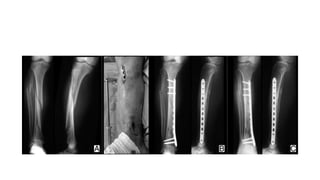

Intra-medullary fixation

-Rx of choice for the most of the type-I, type-II, & type-IIIA Open

& closed tibial shaft #.

-Segmental & bilateral tibial shaft #.

-The ability to lock nails proximally & distally provides control of

length, alignment & rotation in unstable fractures & permits

stabilization of fractures located below the tibial tubercle or 3 to

4cm proximal to ankle joint.

Plate fixation:

- Plating is best for metaphyseal fractures that are unsuitable for

nailing

- The disadvantages of plate fixation included:

(i) the need to expose the fracture site

(ii) Stripping the soft tissues around the fracture. This may

increase the risk of introducing infection and delaying

union.

Close plating:

-The plate is slid across the fracture through proximal and distal

‘access incisions’ on the anterolateral aspect of the tibia and

then fixed to the bone only at these levels.

-This method of ‘submuscular’ plating preserves the soft tissues